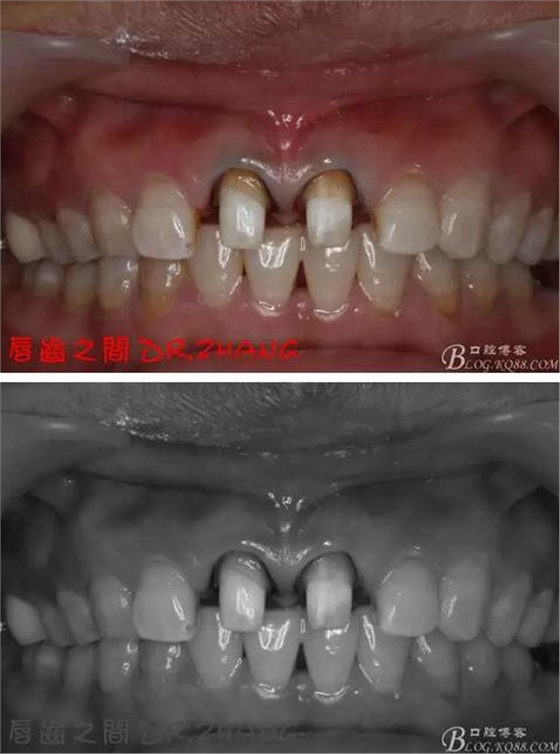

牙體預(yù)備后 硅橡膠取模 臨時(shí)牙恢復(fù)形態(tài)

復(fù)診:臨時(shí)牙良好 患者自訴無(wú)不適癥狀 去除臨時(shí)修復(fù)體 排齦 清理牙面 試戴全瓷修復(fù)體后粘結(jié) 常規(guī)醫(yī)囑 不適隨診

總結(jié):沒(méi)有術(shù)前照片 預(yù)備牙體過(guò)長(zhǎng) 顏色還是有差距